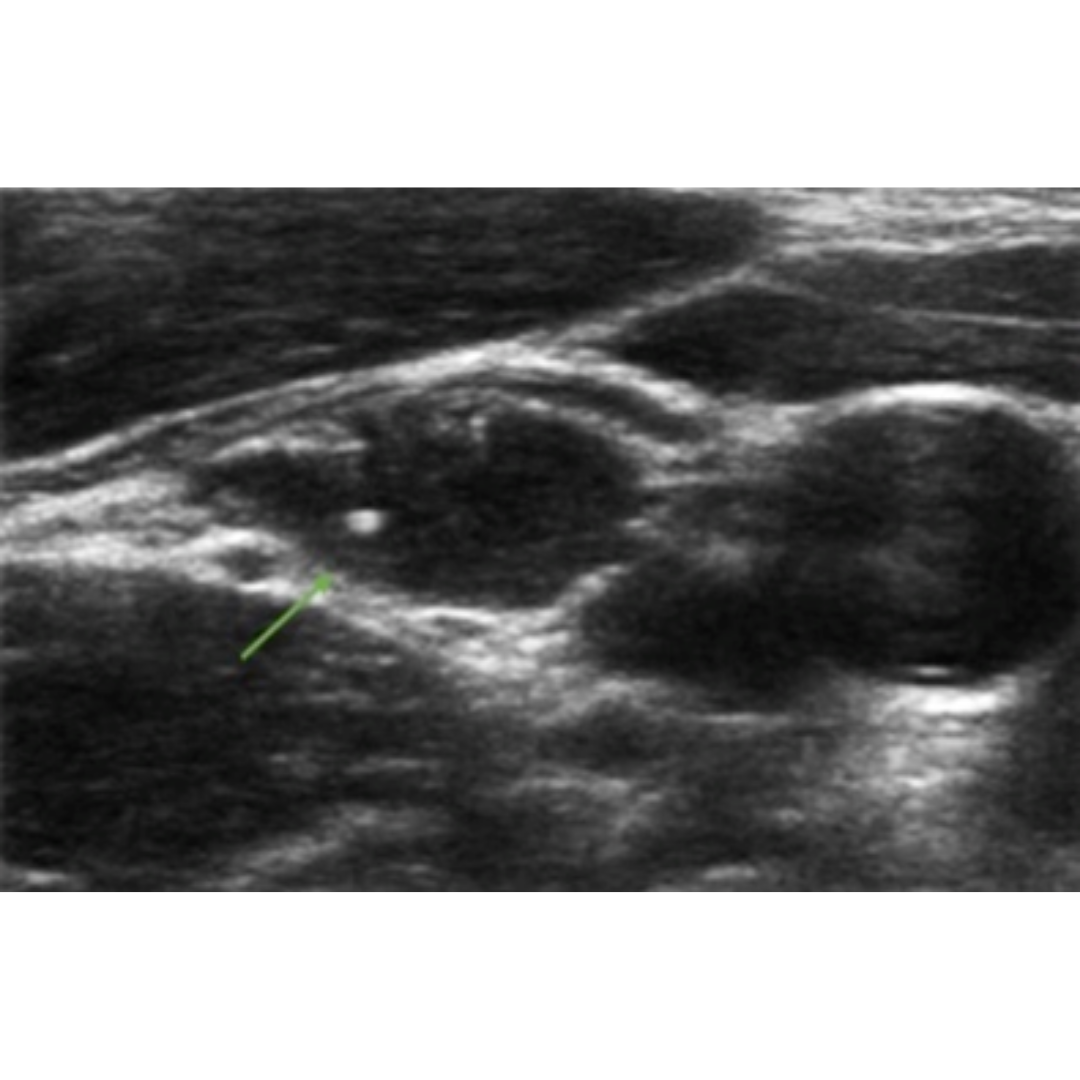

Figura 7. Flechas verdes indican granulomas, que se observan como imágenes hiperecogénicas con sombra acústica posterior y un tenue halo hipoecogénico.